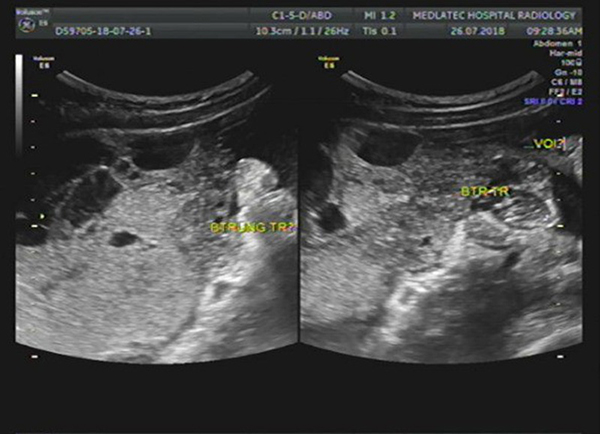

Thực tế siêu âm buồng trứng là một trong những phương pháp sử dụng đầu dò có phát sóng siêu âm để đưa sâu vào âm đạo. Phương pháp này còn được nhiều người gọi với tên khác là siêu âm đầu dò âm đạo. Thông qua kỹ thuật chuyên sâu này, bác sĩ có thể đưa ra đánh giá chính xác về tình trạng của buồng trứng, tử cung và nhiều vùng khác. Bởi phương pháp siêu âm đầu dò buồng trứng mang đến kết quả chẩn đoán chính xác khá cao.

Bên cạnh việc sử dụng sóng siêu âm ở đầu dò để khám buồng trứng, tử cung, phương pháp này còn được áp dụng với nhiều kỹ thuật khác để siêu âm ổ bụng. Với cách siêu âm này, kích thước cũng như tình trạng của buồng trứng sẽ được khám và cho ra kết quả chính xác nhất.

Nhờ áp dụng phương pháp này mà bác sĩ sẽ có thể đưa ra chẩn đoán cũng như kịp thời đánh giá tình trạng của buồng trứng. Nếu nhận thấy sự bất thường của buồng trứng, tử cung như xuất hiện khối u, bác sĩ sẽ kịp thời can thiệp để hạn chế những ảnh hưởng mà người bệnh có thể gặp phải. Vì thế mà quá trình điều trị cũng diễn ra suôn sẻ và đạt hiệu quả cao hơn.